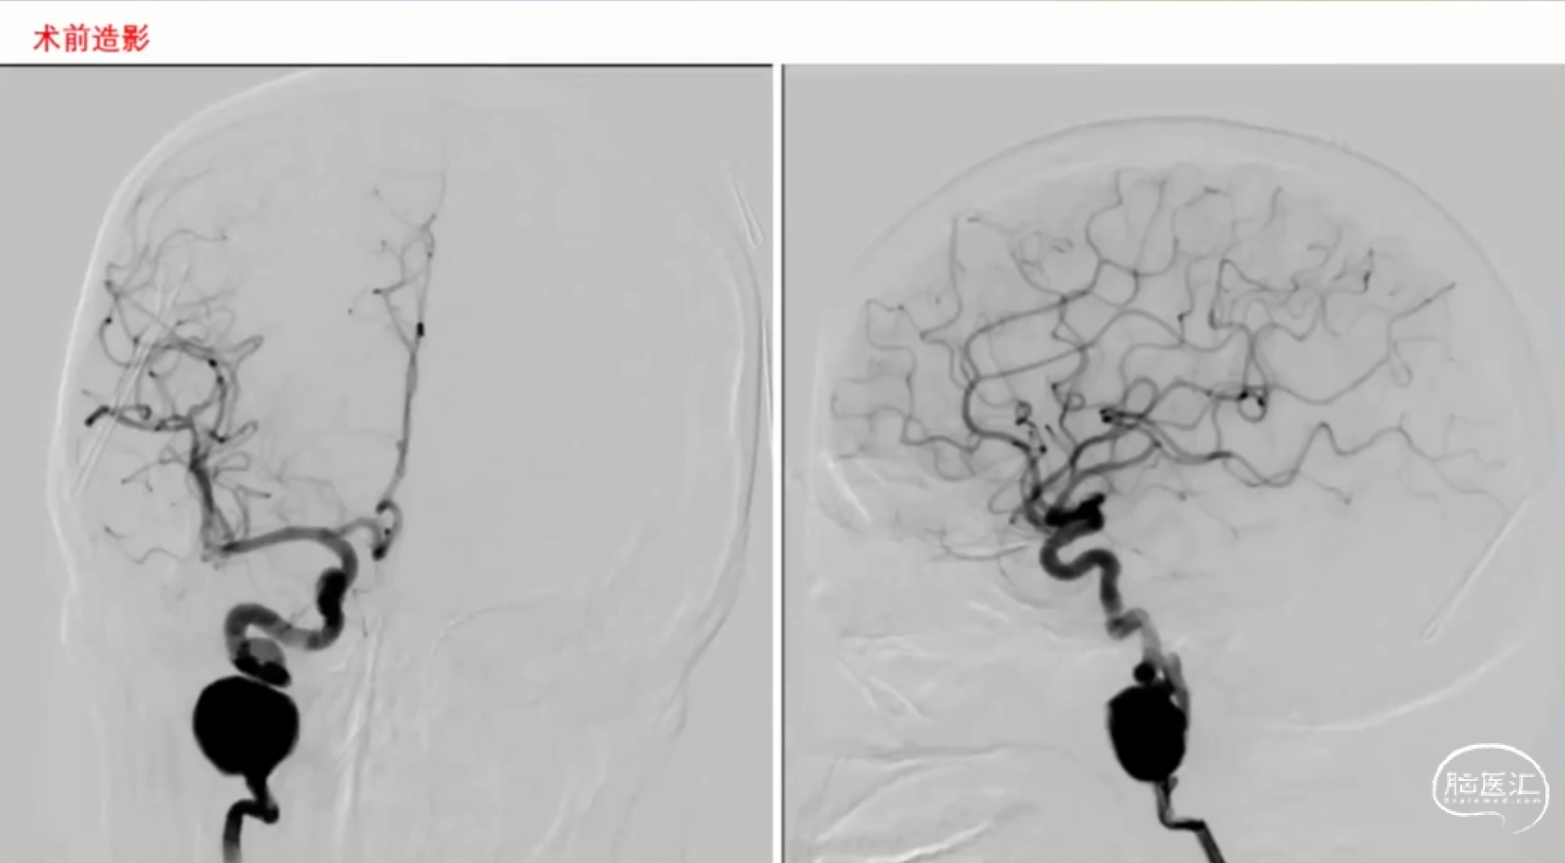

为了拓宽广大医师同道们对神经介入技术的思考维度,精进手术技术,脑医汇特此推出【神经介入-手术视频库】栏目。视频详细展示了术中操作过程,使用不同医疗器械的技巧和注意事项,以及患者的治疗效果等内容。

本期为大家整理了(8.11-9.22)的手术视频精选。欢迎各位同仁观看学习,共同提高诊疗水平,造福更多患者!